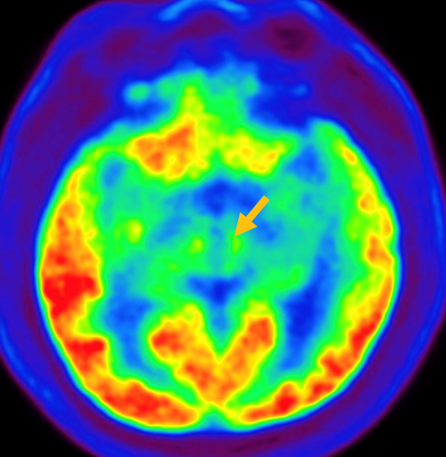

진행 핵상 마비는 대표적인 파킨슨 증후군 중의 하나입니다. 파킨슨병과 다른 점은 질병의 초기부터 중심을 잡기 어려운 체위 불안정이 나타나 자주 넘어진다는 것입니다. 파킨슨병의 경우 질병이 상당히 진행된 뒤에 체위 불안정이 나타납니다. 또한 진행 핵상 마비에서는 목 주위 근육을 비롯한 몸 중심 근육의 경축이 나타나, 목을 뒤로 젖히면서 걷는 모습이 보입니다. 그리고 눈의 운동을 조절하는 기능에 장애가 나타나 아래쪽을 바라보는 데 문제가 생겨 계단을 내려갈 때 어려움을 겪는 경우가 많습니다. 진행 핵상 마비가 의심되는 경우, 뇌 자기공명영상(MRI)에서 중뇌의 위축이 비정상적으로 심하게 나타나는 소견을 확인하거나, 뇌포도당 양전자 단층촬영(PET)에서 전두엽과 중뇌의 대사 기능이 저하된 소견을 확인하여 진단에 참고할 수 있습니다.

[진행핵상마비 환자의 뇌포도당 양전자 단층 촬영에서 확인되는 중뇌의 대사 저하 소견]